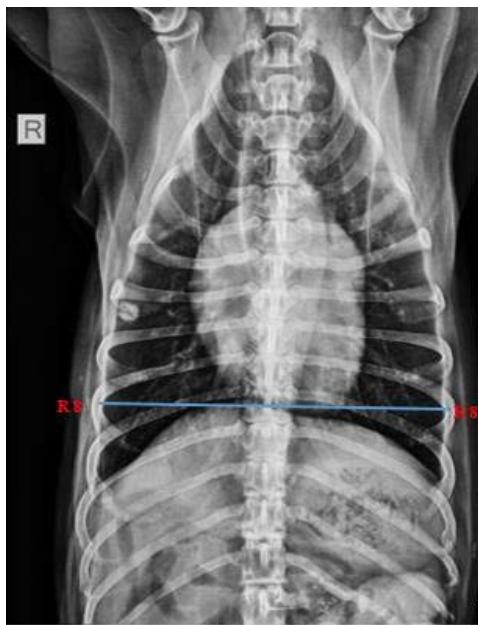

Tracheal Diameter: Tracheal Inlet (TD: TI) ratio was calculated by recording the diameter of the trachea at the level of the thoracic inlet and the inner diameter of the thoracic inlet (Fig 1). Cardiothoracic ratios (CTR) were calculated by dividing the largest width of the thorax by chest depth on radiographs (Fig 3). On a dorsoventral/ventrodorsal radiograph, the width of the thorax was measured as the distance between the medial borders of the eight ribs (Fig 4). The depth was assessed on the right lateral radiographic view from the dorsal margin of the xiphoid process to the ventral margin of the vertebral body, with the electronic calipers aligned perpendicular to the vertebral column. The Vertebral heart score was calculated according to Buchanan and Bucheler, 1995 (Fig 2).

Group I animals had a Cardio-thoracic ratio ranging from 0.73- 1.03, and Group II had a cardio-thoracic ratio ranging from 0.69-1.12. All the animals had CTR values in the normal range irrespective of type of the neoplasm.

Fig. 4: Skiagram showing measurement of thoracic width on ventrodorsal view for assessment of the cardiothoracic ratio

Cardiothoracic ratio, CTR = Largest width of the thorax/Chest Depth = 0.89